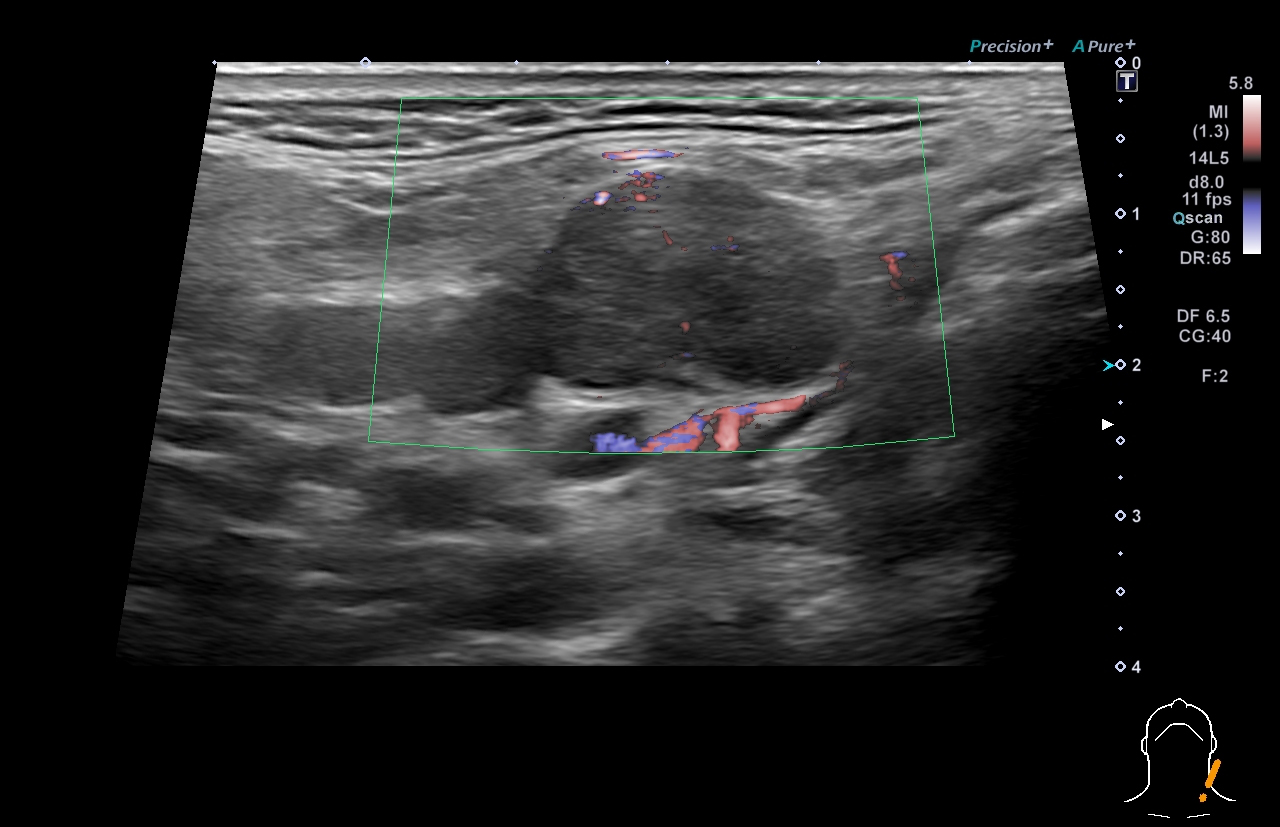

超音波(エコー) 診断画像

- 内頸動脈狭窄

- 膀胱がん

- 粉瘤

- 膝窩靭帯炎

- 乳腺症

- 乳がん

- 転移性肝がん

- 胆嚢ポリープ

- 胆石

- 大腸がん

- 前立腺肥大・前立腺がん

- 静脈瘤

- 腎細胞がん

- 子宮筋腫

- 心エコー(大動脈弁・僧帽弁閉鎖不全症)

- 鎖骨上転移

- 頸部リンパ節転移

- 胃がん

- バセドウ病